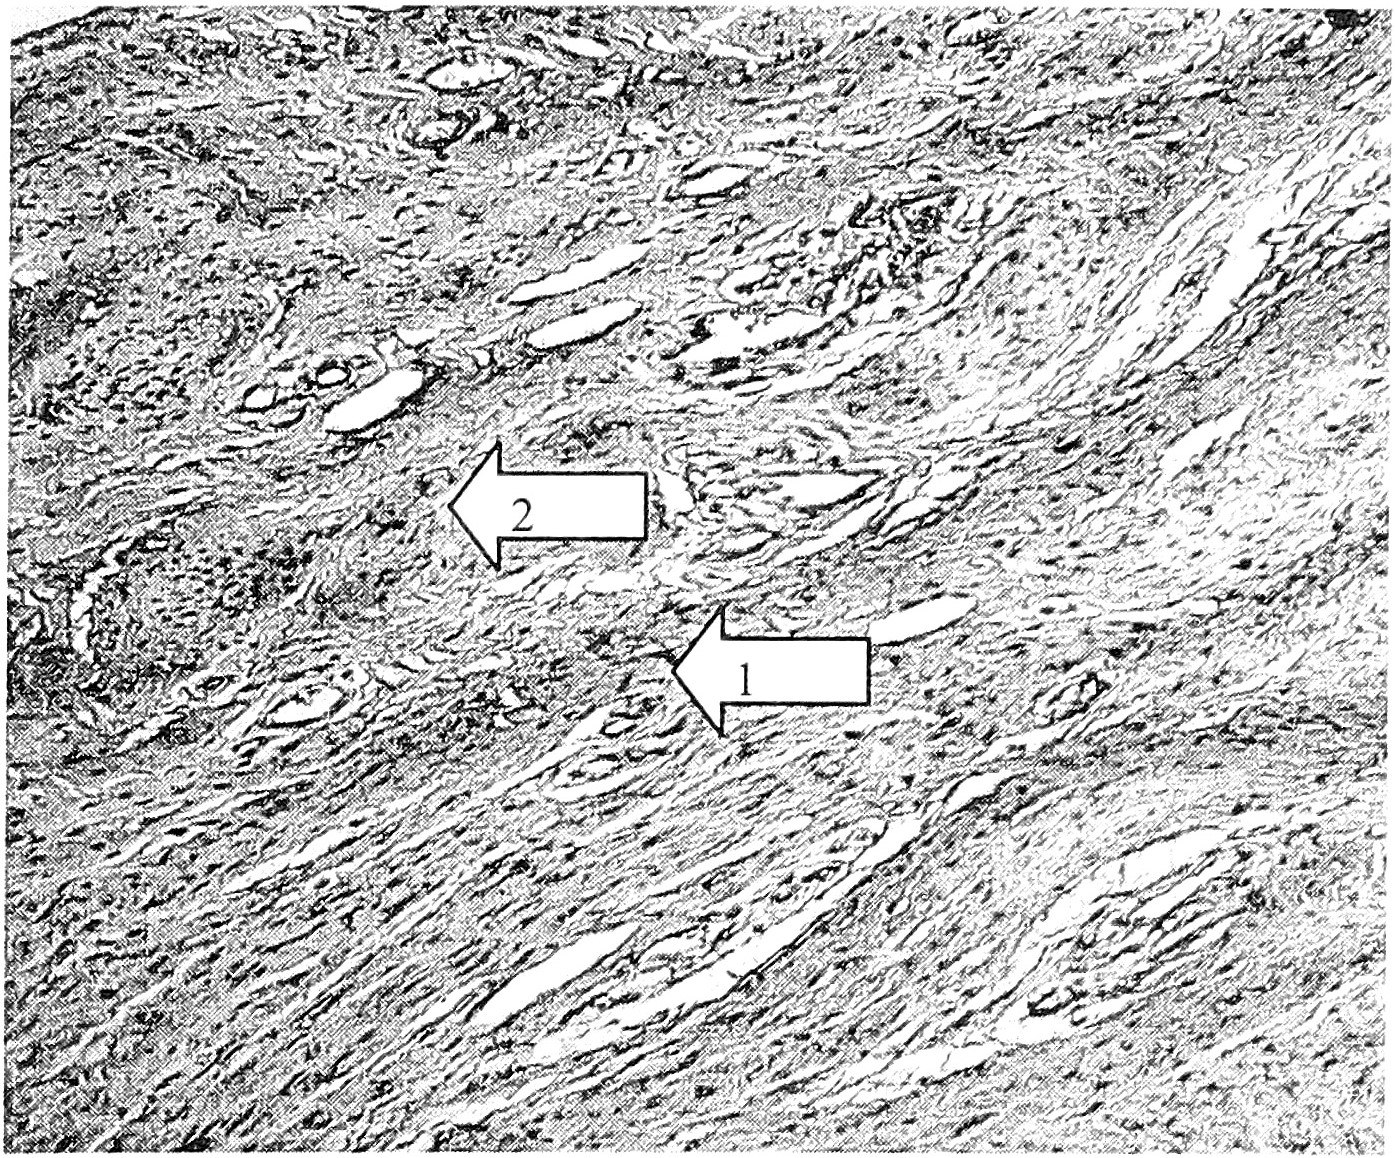

Рис. 2. ЭШМ I степени, ДСТ легкой степени (пациентка 34 лет). Выраженная экспрессия коллагена I типа в строме (1) и в мышечной ткани (2) шейки матки. Ув. 100.

Иммуногистохимическим исследованием установлены топографические, количественные, качественные особенности коллагенообразования и фибропластики при ЭШМ с проявлениями ДСТ в сравнении с контрольным наблюдением.

Характерно относительное снижение экспрессии антител к коллагену I типа в строме, стенках сосудов и повышение ее в пучках мышечных волокон и вокруг лейомиоцитов. В этих же структурах, как в поверхностных, так и в глубоких отделах шейки матки, повышаются и имеют распространенный характер экспрессируемые коллагены III и IV типов (рис. 1, 2, 3).